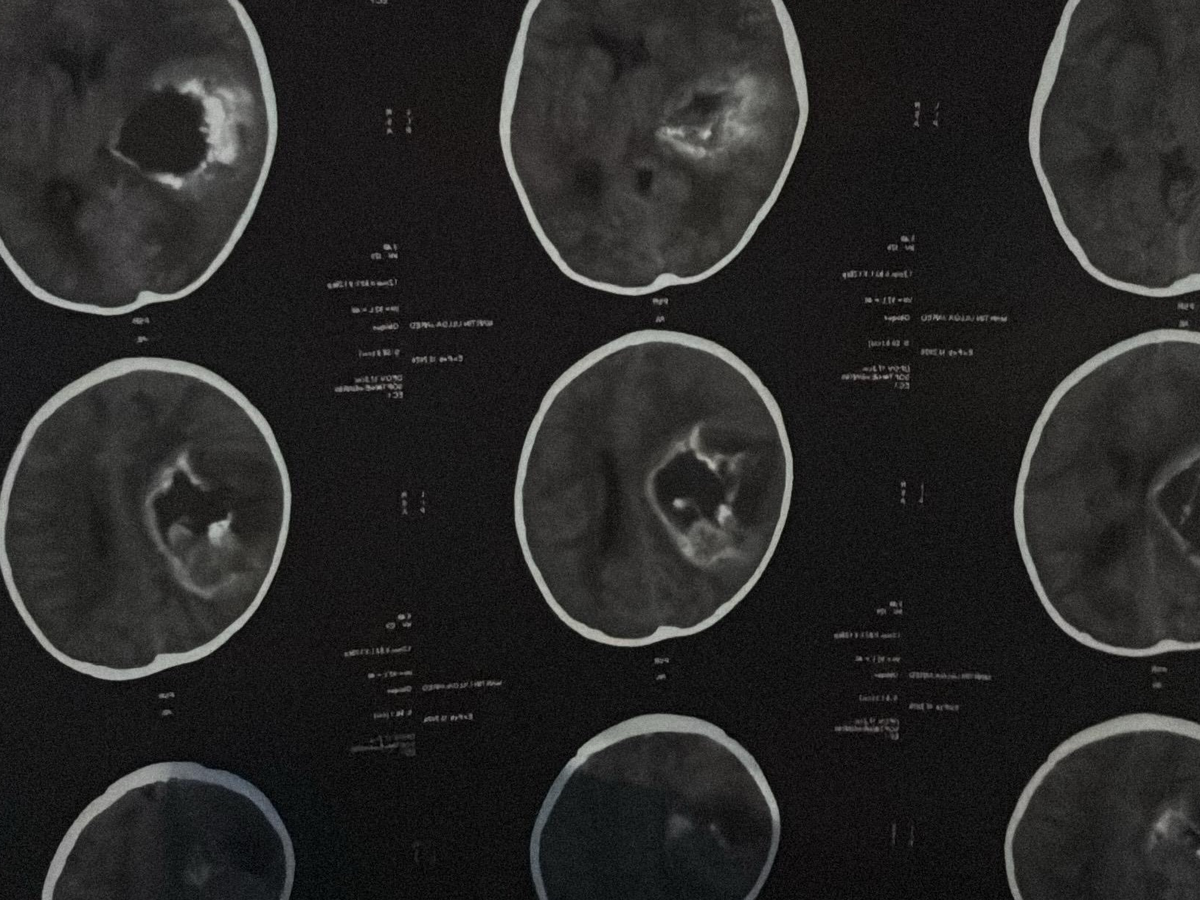

Our sweet 1-year-old has been diagnosed with a massive brain tumor affecting nearly half of his brain.

He suddenly became unresponsive, and doctors discovered a large tumor in the right side of his brain causing dangerous swelling and pressure. He had to be intubated to protect his breathing and is currently fighting for his life.

Nuestro bebe de solo 1 año fue diagnosticado repentinamente con un tumor cerebral muy grande que afecta casi la mitad de su cerebro. El tumor provocó una inflamación severa y una presión peligrosa en su cerebro, y dejó de responder. Los médicos tuvieron que intubarlo para proteger su vida.